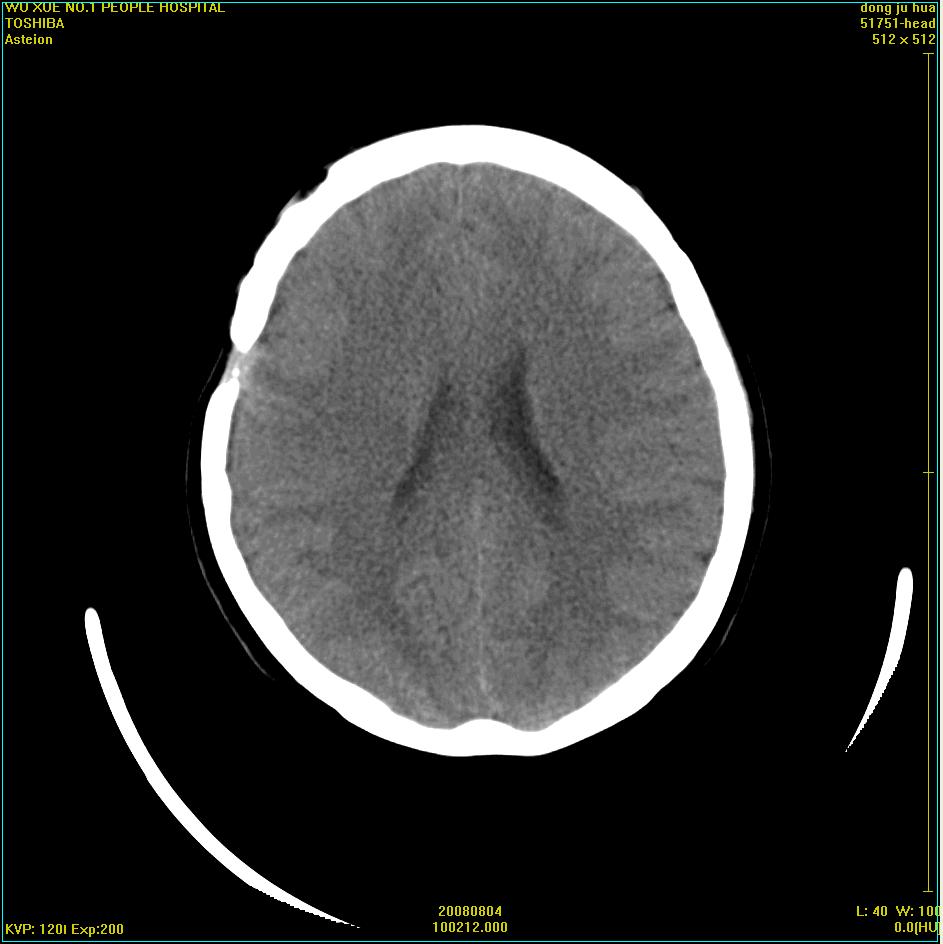

患者,女,45岁。四年前在我院做ct诊断为右侧桥小脑脚区三叉神经鞘膜瘤,已做手术。今复杳。请大家看看

三叉神经鞘膜瘤术后

考虑三叉神经鞘膜瘤术后复发并瘤体内出血。

三叉神经鞘膜瘤术后复发并瘤体内出血

考虑慢性扩张性血肿吧!请大家再看看,发表高见!

考虑:三叉神经鞘膜瘤术后复发并瘤体内出血。支持!

术后病例最好直接增强。

四年前做的手术,为什么大家不考虑慢性颅内血肿呢?

考虑慢性颅内血肿?症状体征有多少?能否发上?